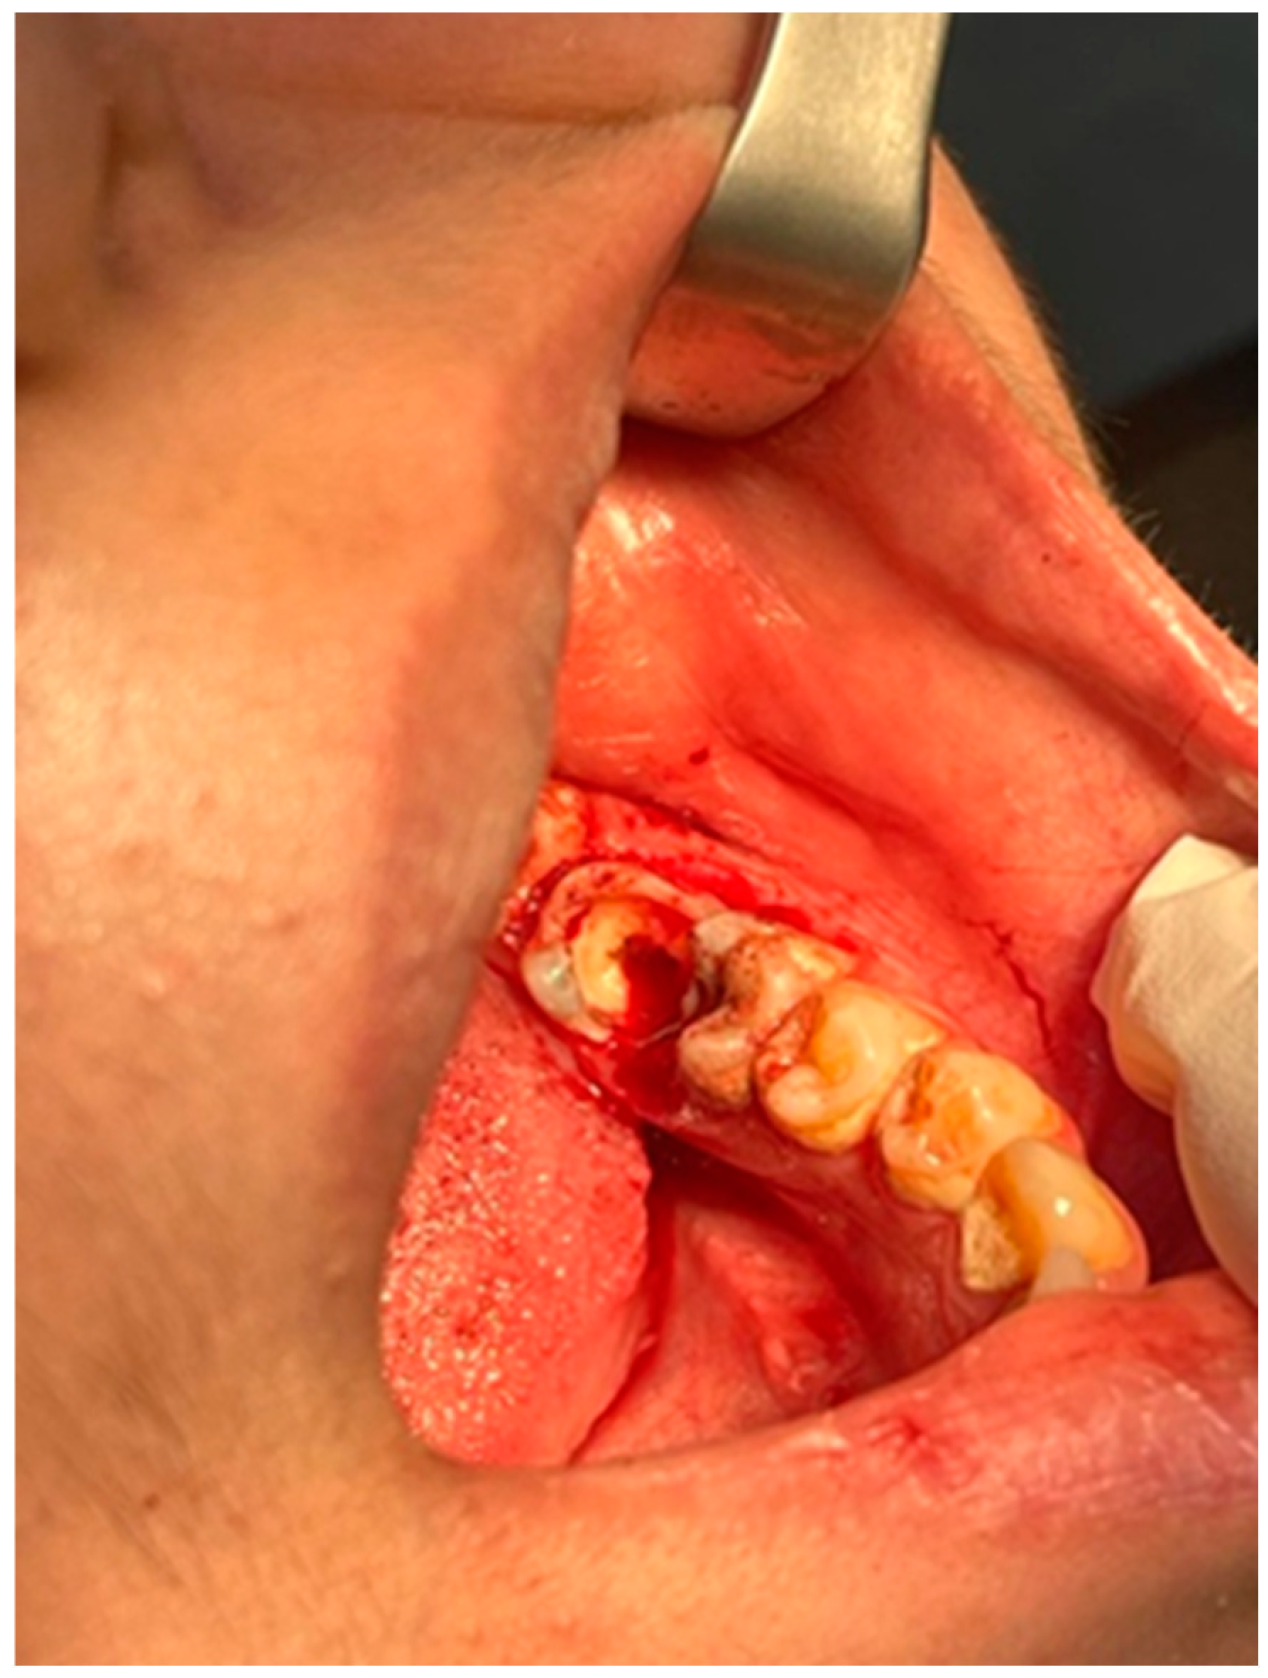

2.2. Clinical Examination

2.4. Surgical Management